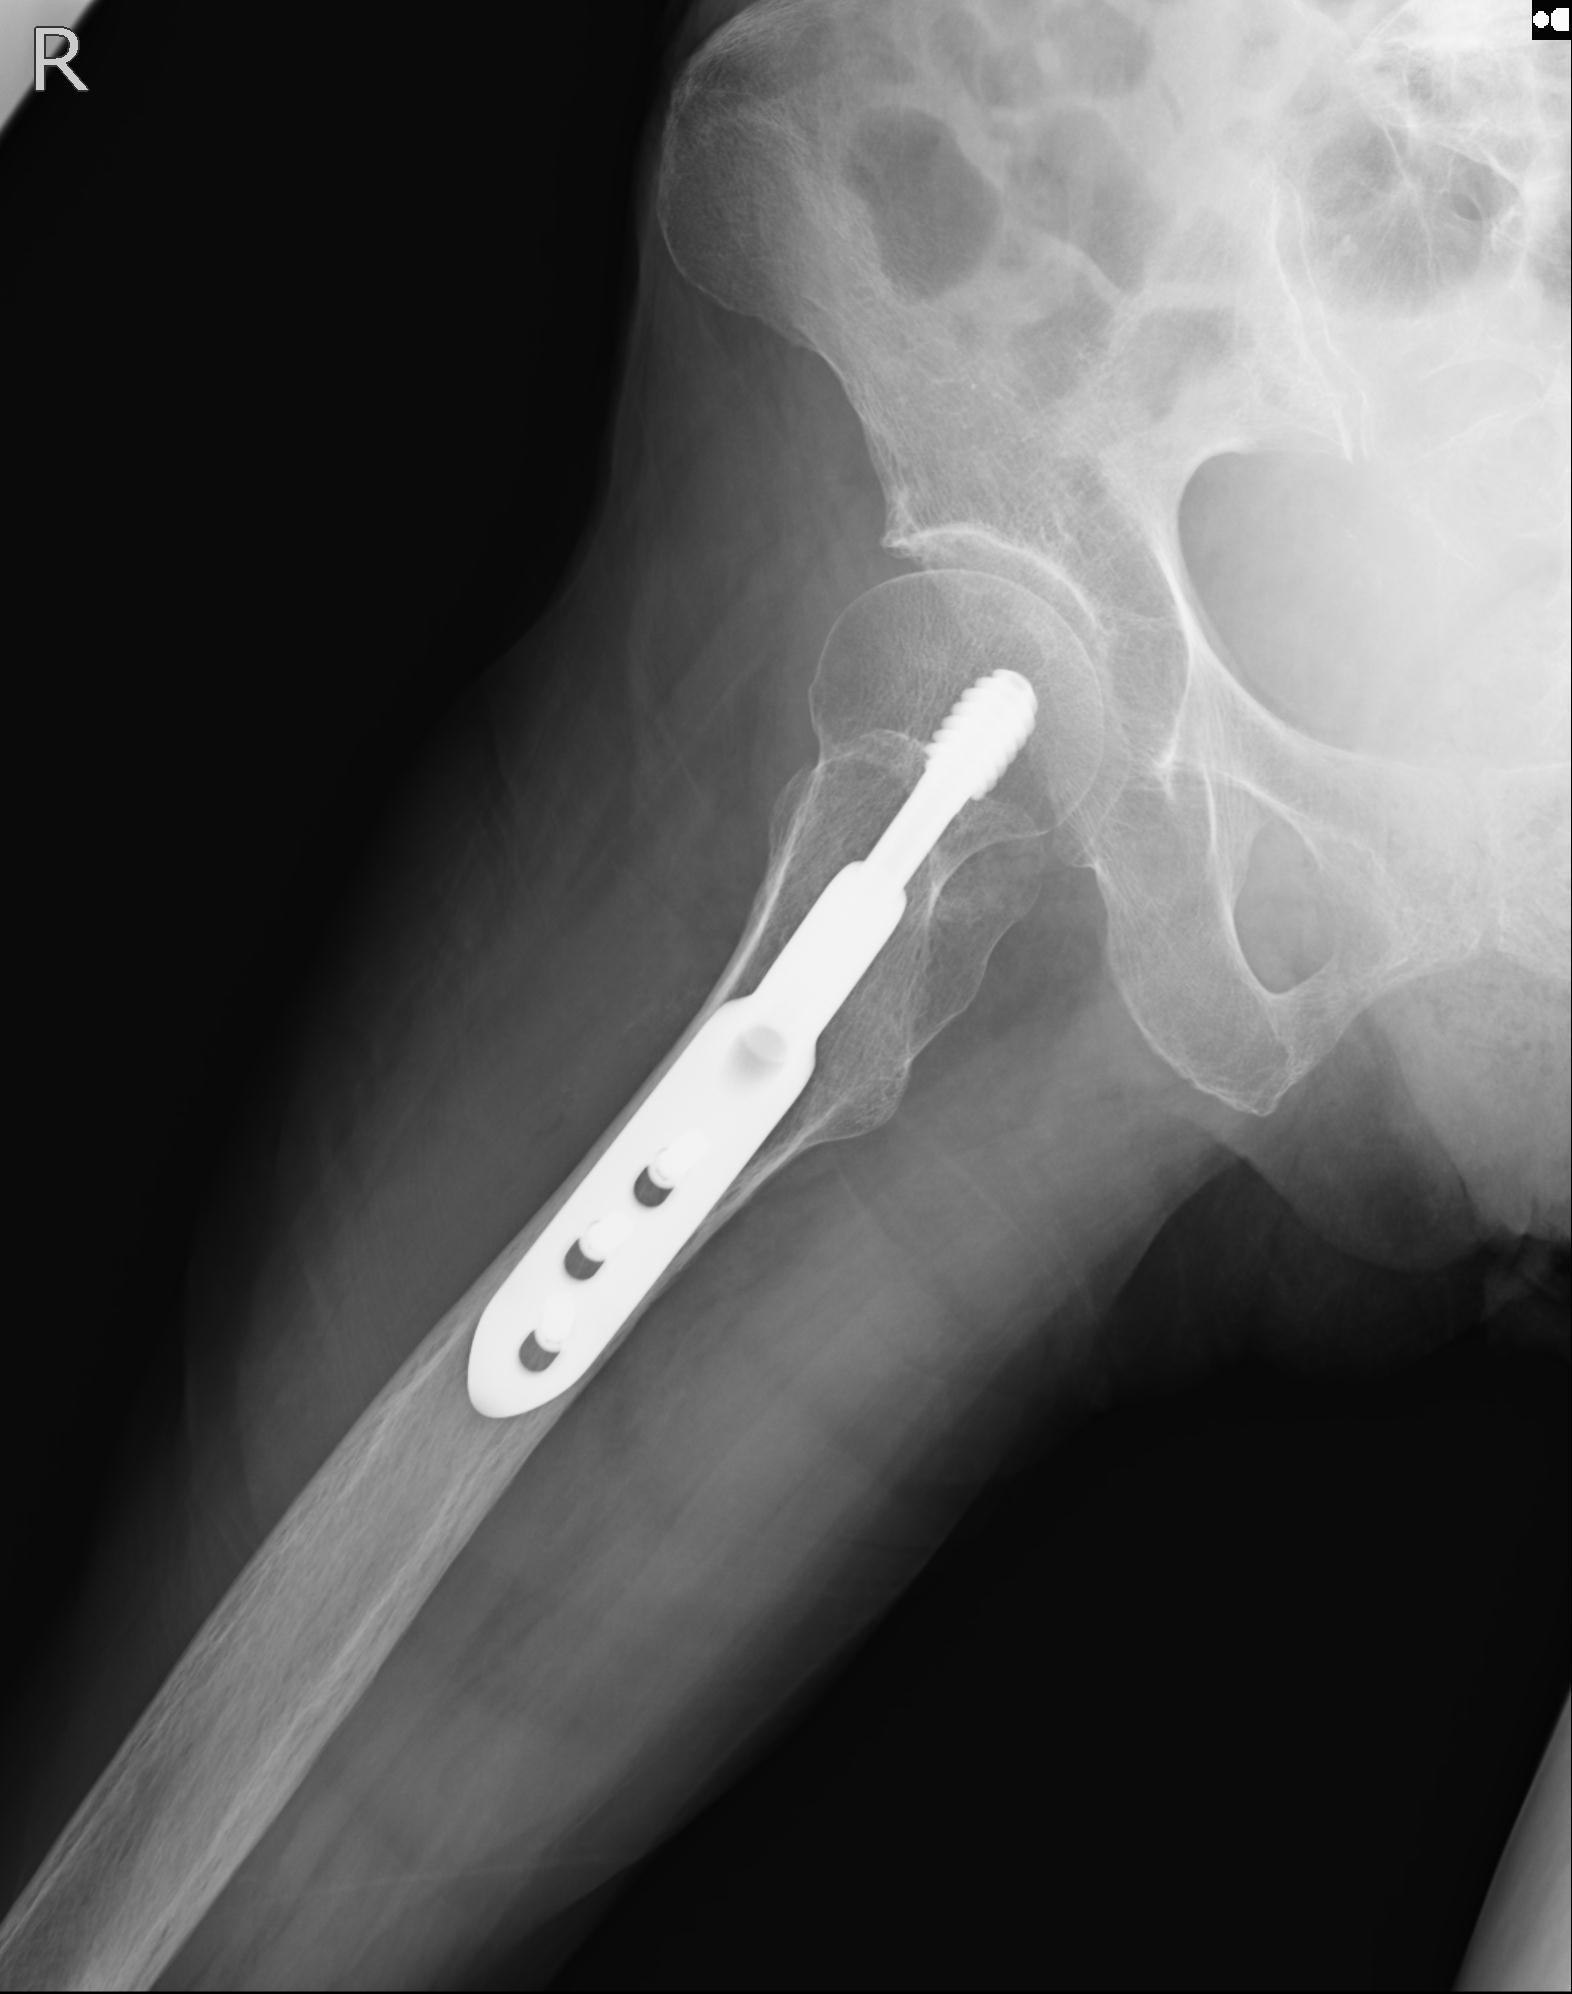

102811 1/13 股関節 2R 1/19 2R 80歳女性 右DHS